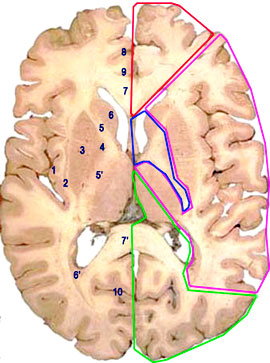

Coupe frontale du cerveau (Charcot)

- Le groupe intermdiaire provient de plusieurs sources : la sylvienne, la communicante postrieure et la chorodienne antrieure. Leurs rameaux superficiels irriguent la zone centrale du losange opto-pdonculaire.

Les rameaux perforants constituent le groupe des artres stries, ils se distribuent au striatum (noyau caud et putamen), aux noyaux ventro-latraux et antrieur du thalamus, ainsi qu' la capsule interne.

Les perforantes issues de la chorodienne antrieure se destinent principalement la partie mdiale du noyau lenticulaire (globus pallidum).

- Le groupe postrieur est fourni par lartre crbrale postrieure. Deux contingents dartrioles sen dtachent : les rameaux thalamo-mamillaires, pour les tubercules mamillaires et la rgion dorsale du thalamus. Le groupe thalamo-genouill irrigue les corps genouills latraux, le pulvinar, le segment rtro-lenticulaire et le bras postrieur de la capsule interne, la portion temporale du noyau caud, ainsi que les radiations optiques.

-a et b: perforantes antrieures

-c et d: perforantes intermdiaires

-e: groupe postrieur

cc: corps calleux

-ci: capsule interne

-v: 3 ventricule

-v': ventricule latral

-1: noyau lenticulaire

-2: noyau caud

-3: noyaux hypothalamiques

-4: artre crbrale moyenne

-5: artres stries

-6: artre pricalleuse

-7: artre calloso-marginale